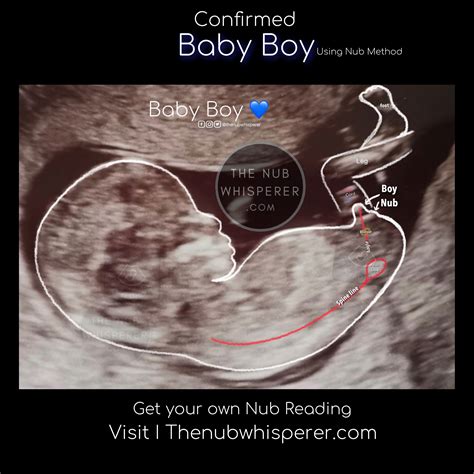

• 13 weeks pregnant gender prediction

• 13 week ultrasound pictures gender

• 13 weeks pregnant ultrasound gender